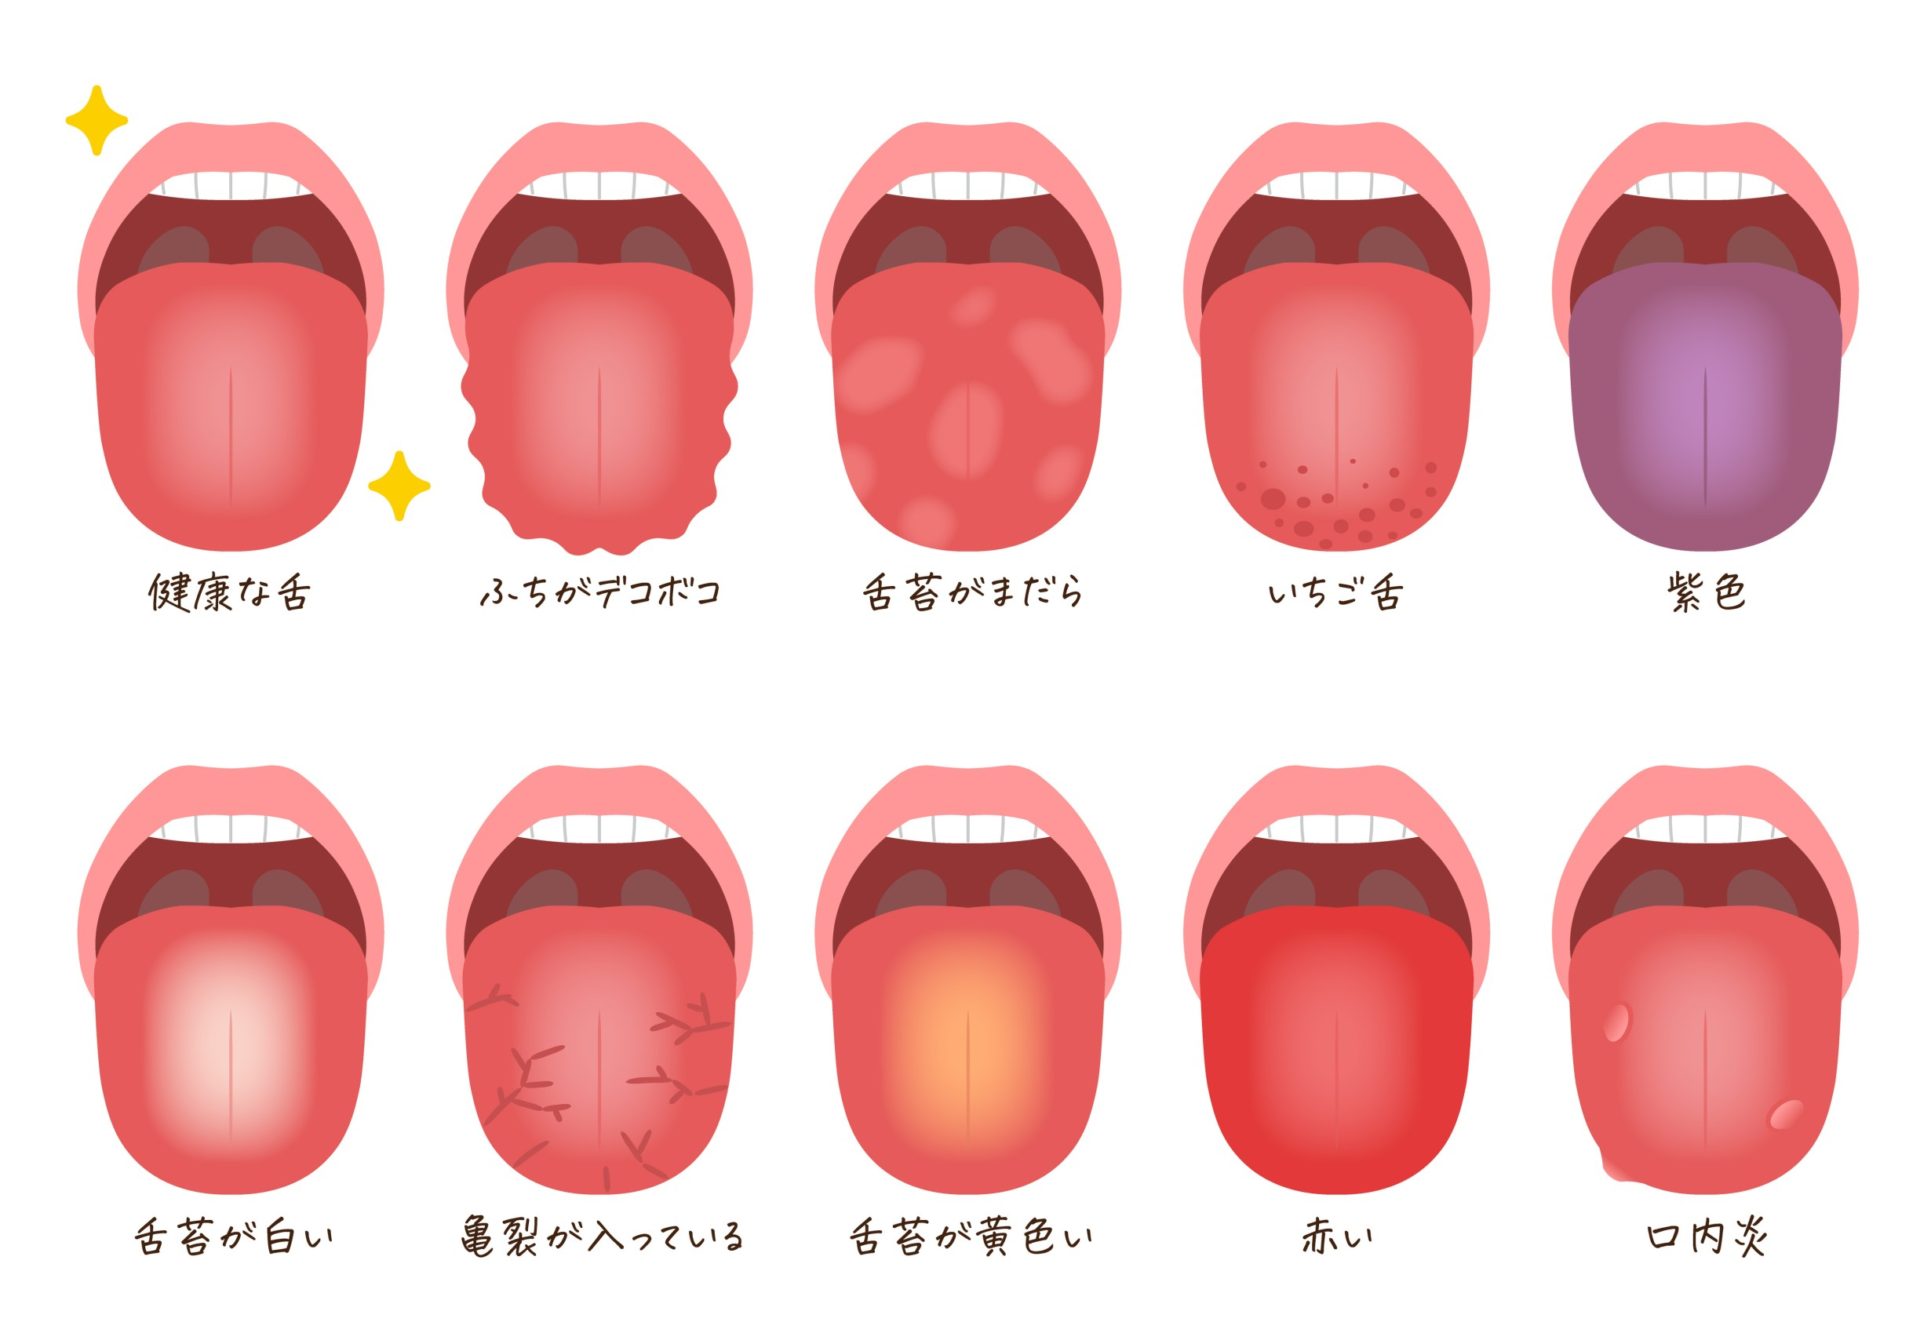

体調が丸わかり"危険な舌"の状態はこれだ 舌は「健康のバロメーター」週刊女性PRIME東洋経済オンライン。

白い、ガタガタ、ひび割れ 。“舌”でわかる体調不良のサインとは?田中友也さん 季節の養生法からだにいいこと。

舌のサイン 院長ブログ八尾市のオカモト鍼灸整骨院。

舌診~毎日鏡の前で健康チェックをしたくなる舌の状態を解説 祥泉針灸整骨院。

石豆。舌は健康のバロメーター三越前駅小伝馬町歯科 ハルデンタルオフィス。

石豆。舌は健康のバロメーター三越前駅小伝馬町歯科 ハルデンタルオフィス。